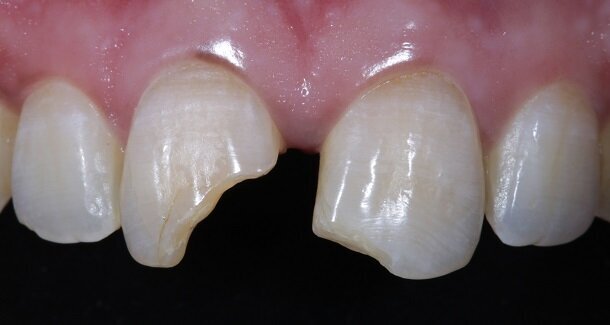

Presenting a case of a 22 yr old male, who reported to our dental office with fractured Maxillary Central incisors many years ago [Figures 1 and 2]. On examination both Maxillary Central incisors had fractures with pulp exposures. IOPAR showed large peri-apical lesions in both teeth. There was no mobility seen in either teeth, but discolouration was seen in both. Non-surgical Endodontic treatment followed by Bleaching and Direct composite restorations (2 weeks post bleaching) were planned.

The figures show the clinical work flow involved. In the 1st appointment Oral prophylaxis, oral hygiene instructions were followed by an impression that was sent to the lab for a wax up [Fig 3 and 4]. In the subsequent appointments, Endodontic treatment was followed by Intra and extra coronal office bleaching using the Pola office bleaching kit. After two weeks, the shade stabilised post bleaching. Shade selection, rubber dam isolation and preparation was done on both the teeth to receive Direct composite veneers so as to close the midline diastema as well as correct the fractured teeth and the slight mal-alignment. Controlled Body Thickness (CBT) technique of layering was used with 3M Z350XT shades - Dentin shades A3, A2 and Enamel shades A2, clear translucent [Figures 5 to 11]. This was followed by the Finishing and polishing protocol as described in the figures.